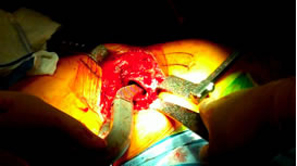

Good fit of final stem.

Stability was very impressive |

Trial neck off the final implant then 8 mm varus neck was chosen for final implantation.

Pt. doing well first day post-op. Saving all the lateral structures was very impressive.